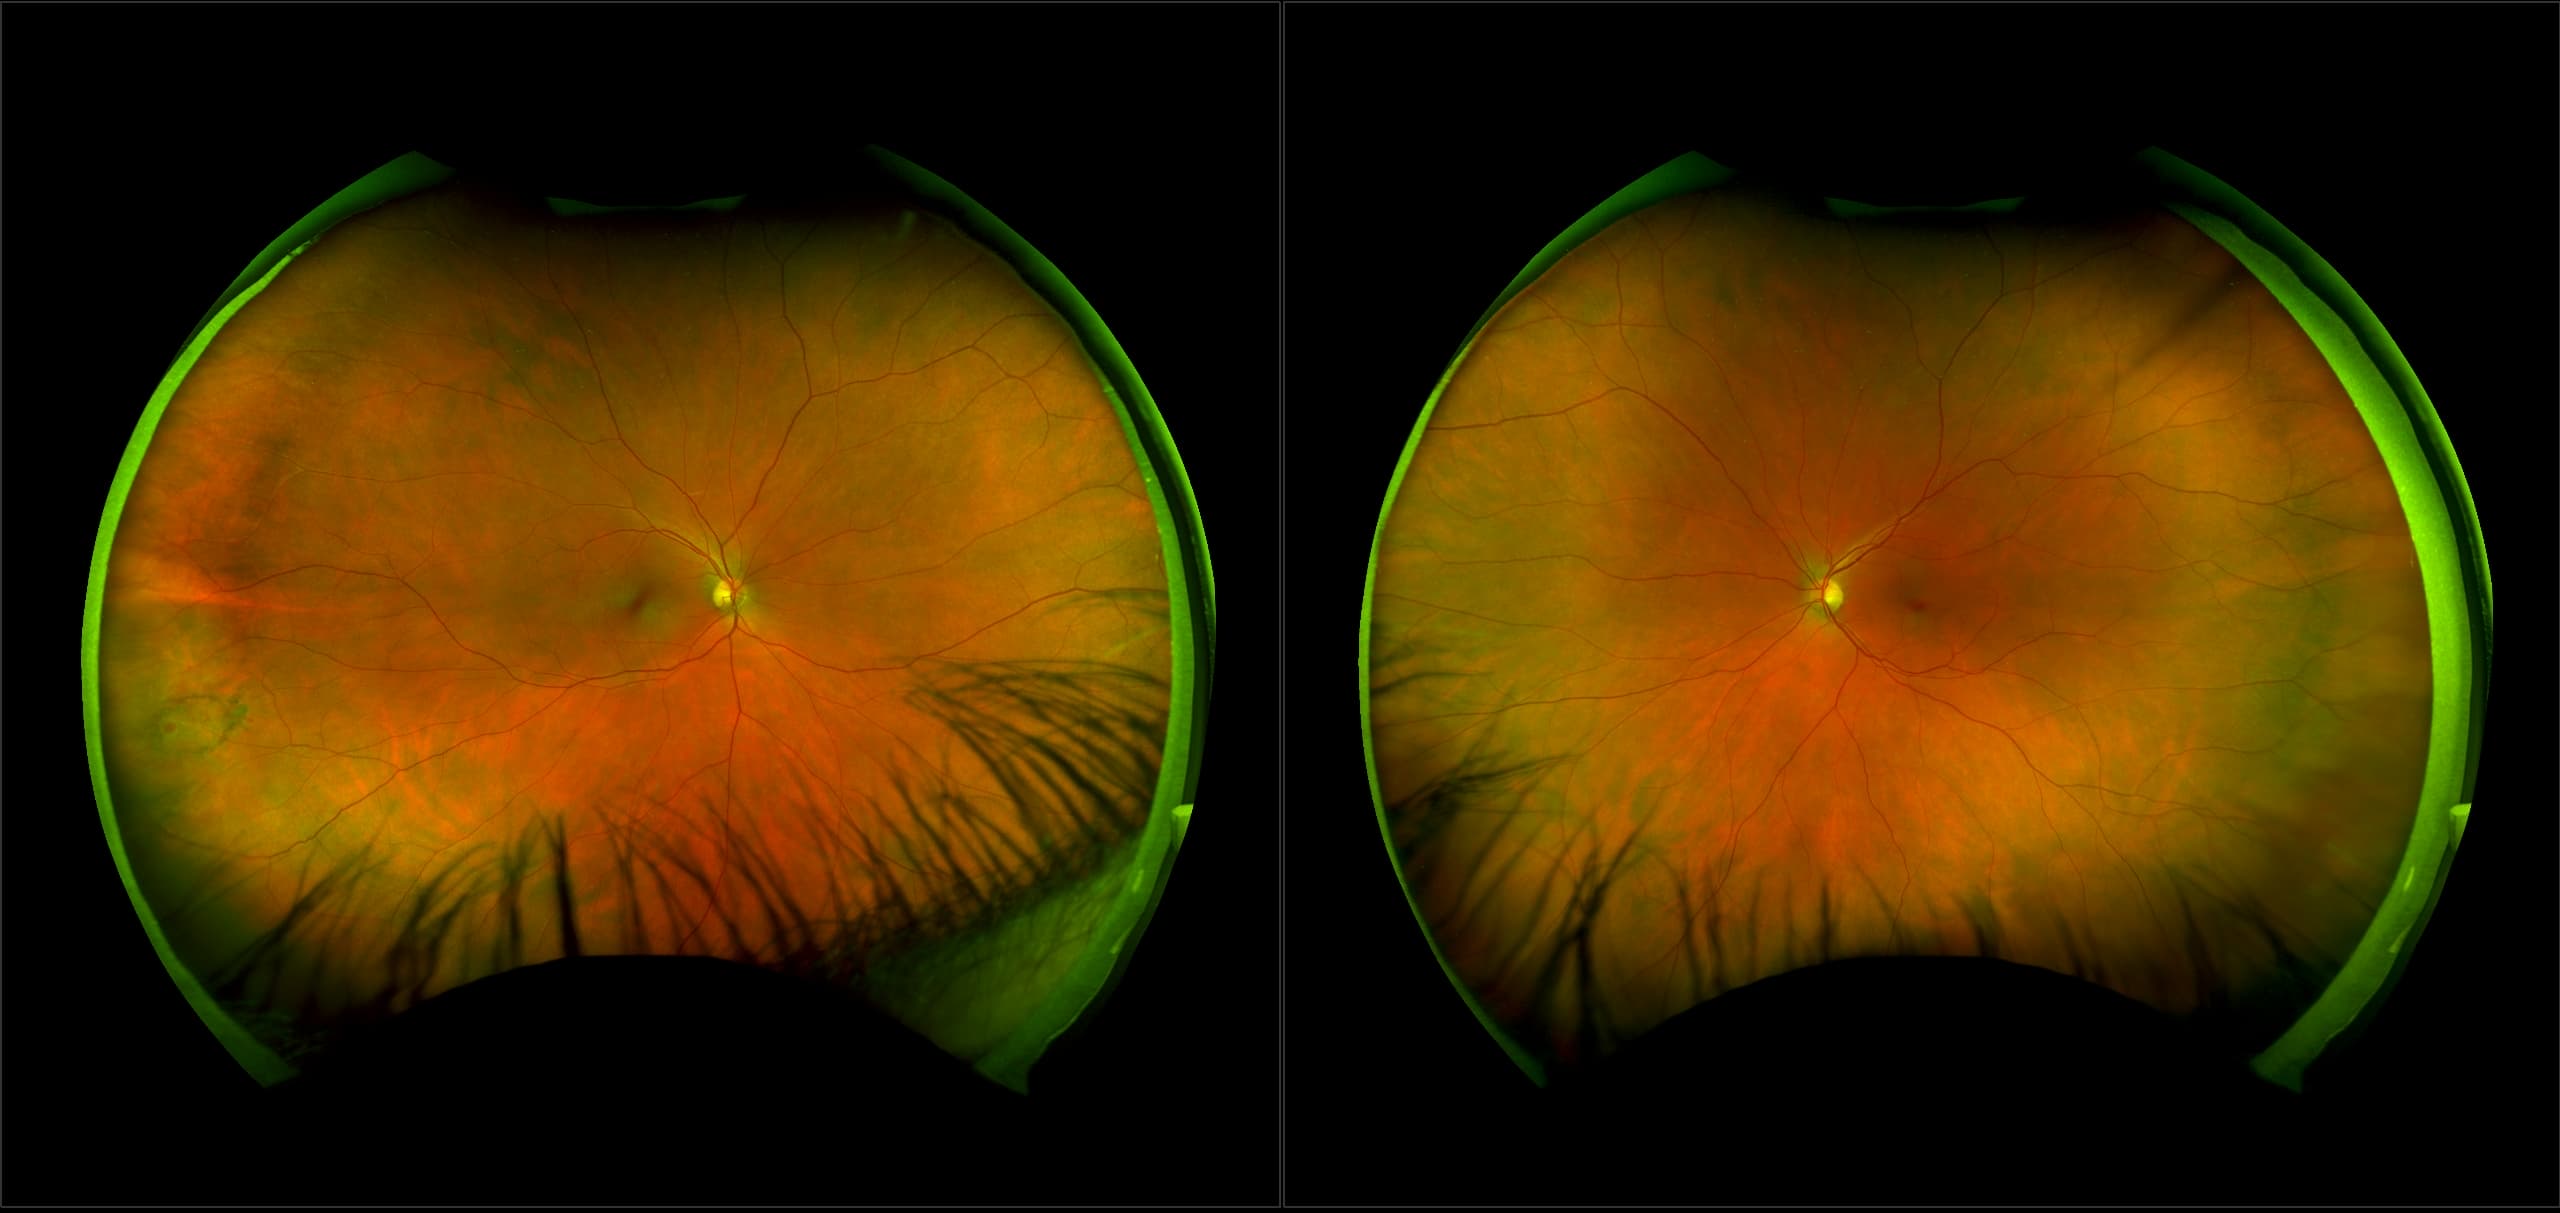

Monaco - Pigment Epithelial Detachment, RG, OCT

In some eyes, there may be small areas of the retina that are torn, or holes may develop. These areas, called retinal breaks, can lead to retinal detachment. Retinal breaks are often caused by traction from the vitreous, the gel that fills the back of the eye. Traction can occur as the vitreous pulls away from the retina, which occurs with age, trauma, surgery, inflammation, and near-sightedness.